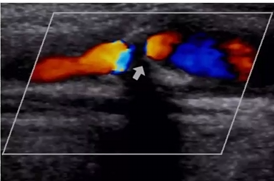

explain the disease process in the vertebral artery documented in this clip (Cant see it in the photo but the video has the flow jump from antegrade to retrograde as it pulses)

Since the usual antegrade flow is switching to retrograde, it suggests subclavian steal

You obtain these images of vertebral arteries.

1. What is this finding right side?

2. What does this indicate?

3. Where is obstruction?

4. Vertebral artery feeds which portion of brain?

5. The two vertebral arteries unite to form?

retrograde flow

subclavian steal

Right subclavian artery that’s proximal to the origin of the vertebral artery

posterior portion

Basilar artery